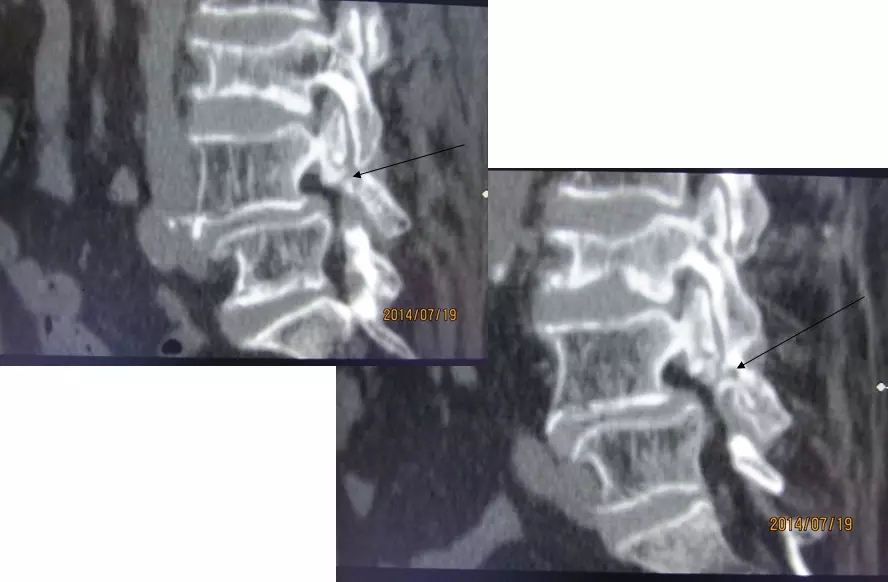

4.滑脱、峡部裂

病因分类

发育不良

缺血

退变

创伤后

代谢性

医源性

分级

I:滑移<25%

II:25%<滑移<50%

III:50%<滑移<75%

IV:75%<滑移<100%

V:滑移>100%

腰椎前滑脱I度

椎弓峡部裂